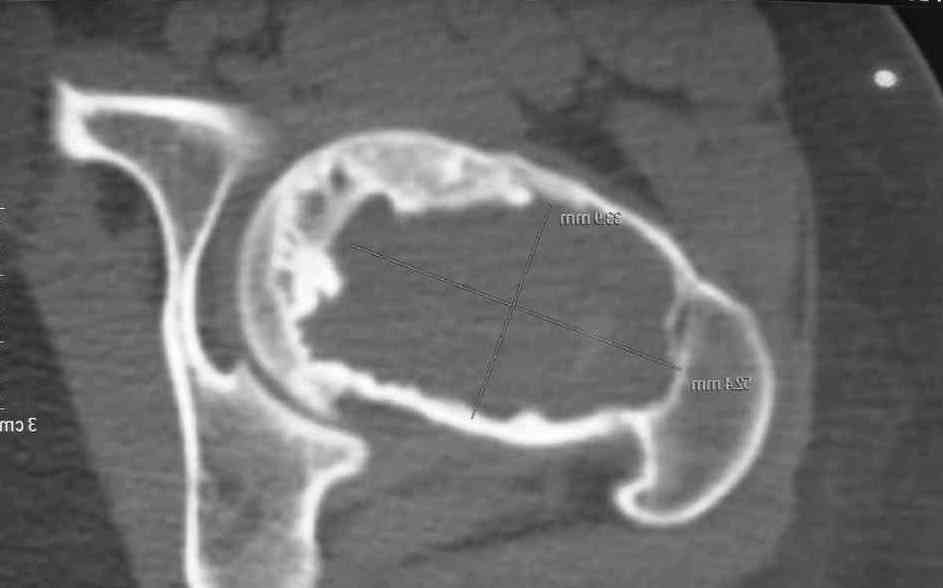

Больная Л.,   23 года.

Из анамнеза:со слов больной в 2006 г. появились боли правой н/конечности, обратилась поместу жительства к хирургу, было выполнена МРТ поясничного отдела позвоночника,назначено физиолечение. Через 2 месяца боли прекратились, через 4 месяца рецидивболевого синдрома. С 2006 – 2010 проводилось консервативное лечение по поводуостеохондроза поясничного отдела позвоночника. В октябре 2010 г. боли усилились.Выполнены Ro и КТправого тазобедренного сустава, выявлен очаг патологической перестройки. Быланаправлена на консультацию в УНИИТО.

В УНИИТО виюне 2011 г. поставлен дифференциальный диагноз между фибромой, солитарной костнойкистой и гигантоклеточной опухолью.